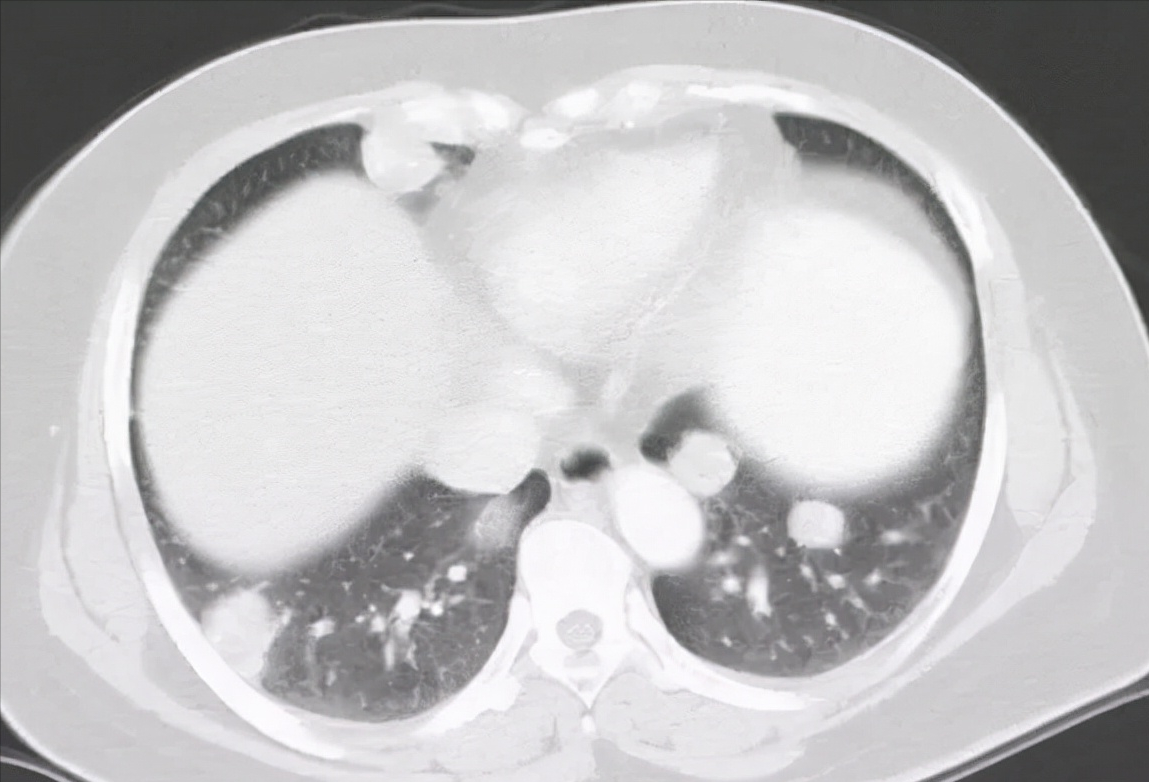

前几天 , 一个35岁女性因为咳嗽、间断咯血一周来门诊就诊 , 常规验血常规 , 做胸部CT , 胸部CT显示右肺一个3.5cm肿块 , 这种单发的不规则肿块 , 恶性可能性很大 , 在问诊过程中 , 仔细询问了她整个发病经过和既往的病史 , 一个细节引起了我的注意 。

绒癌肺转移灶一般为多发结节 , 早期可表现为不规则的小片状影或磨玻璃样阴影 , 随着HCG的升高 , 表现为边缘光滑、密度均一的多发结节 。 但绒癌肺转移灶也会出现单个病灶 , 需要临床医生仔细询问病史以利于鉴别 。